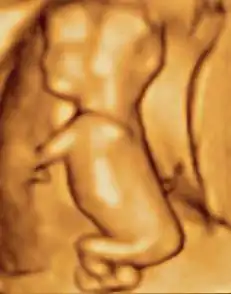

A fetus or foetus (/ˈfiːtəs/; pl.: fetuses, foetuses, rarely feti or foeti) is the unborn offspring of a viviparous animal that develops from an embryo.[1] Following the embryonic stage, the fetal stage of development takes place. Prenatal development is a continuum, with no clear defining feature distinguishing an embryo from a fetus. However, in general a fetus is characterized by the presence of all the major body organs, though they will not yet be fully developed and functional, and some may not yet be situated in their final anatomical location.

In human prenatal development, fetal development begins from the ninth week after fertilization (which is the eleventh week of gestational age) and continues until the birth of a newborn.

In humans, the fetal stage starts nine weeks after fertilization.[11] At this time the fetus is typically about 30 millimetres (1+1⁄4 in) in length from crown to rump, and weighs about 8 grams.[11] The head makes up nearly half of the size of the fetus.[12] Breathing-like movements of the fetus are necessary for the stimulation of lung development, rather than for obtaining oxygen.[13] The heart, hands, feet, brain, and other organs are present, but are only at the beginning of development and have minimal operation.[14][15] Uncontrolled movements and twitches occur as muscles, the brain, and pathways begin to develop.[16]